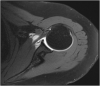

The rotator cuff is a group of four muscles and tendons surrounding the shoulder joint providing it strength and stability. The rotator cuff consists of the subscapularis, supraspinatus, infraspinatus and teres minor. Many shoulder complaints are caused by rotator cuff pathology such as impingement syndrome, tendon tears and other diseases e.g. calcific tendonitis. Diagnosis starts with clinical history and physical examination, after which imaging is often used to help confirm clinical findings depending on the differential diagnosis. The aim of the article is to review the frequently used imaging modalities to assess the rotator cuff and cuff-related disease, specifically focusing on radiography, ultrasonography and magnetic resonance imaging. This article will outline the advantages and disadvantages for each modality and illustrate typical radiological findings of common rotator cuff pathologies.